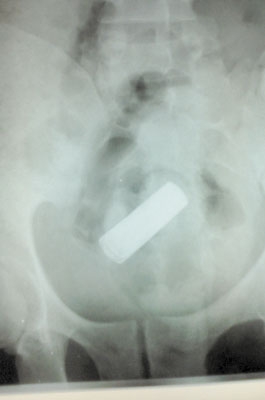

BIZARRO - Imagem de raio-x mostra pilha introduzida no corpo do rapaz

Um homem de 32 anos introduziu uma pilha tamanho grande no ânus. A vítima não quis detalhar como o objeto foi parar lá, mas teve que passar por atendimento no “Janjão” e na Santa Casa. O problema só foi resolvido com laxante.

O caso aconteceu na semana passada, mas só revelado quarta-feira. Exames mostraram que o objeto estranho ficou parado no intestino, onde causou uma infecção grave. Após expelir a pilha, o paciente foi liberado.